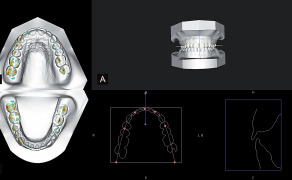

- Opisano przypadek pacjenta z przodozgryzem rzekomym leczonego z zastosowaniem protokołu Alt-Ramec w celu wspomagania wysunięcia szczęki.

Streszczenie: W terapii klasy III istotne jest leczenie interceptywne. Opisano przypadek pacjenta z przodozgryzem rzekomym leczonego z zastosowaniem protokołu Alt-Ramec w celu wspomagania wysunięcia szczęki. Osiągnięto korektę odwrotnego nagryzu i potwierdzone cefalometrycznie ortopedyczne wysunięcie szczęki.

Stosowane metody leczenia obejmują próbę wysunięcia szczęki w celu uzyskania dodatniego nagryzu poziomego. Jeśli retrognacji towarzyszy zwężenie szczęki, w planie leczenia uwzględnia się jej rozbudowę.

U pacjentów, którzy nie wymagają znacznego poszerzania szczęki, zastosowanie może znaleźć metoda Alt-Ramec. Protokół leczniczy Alt-Ramec (alternating rapid [...]